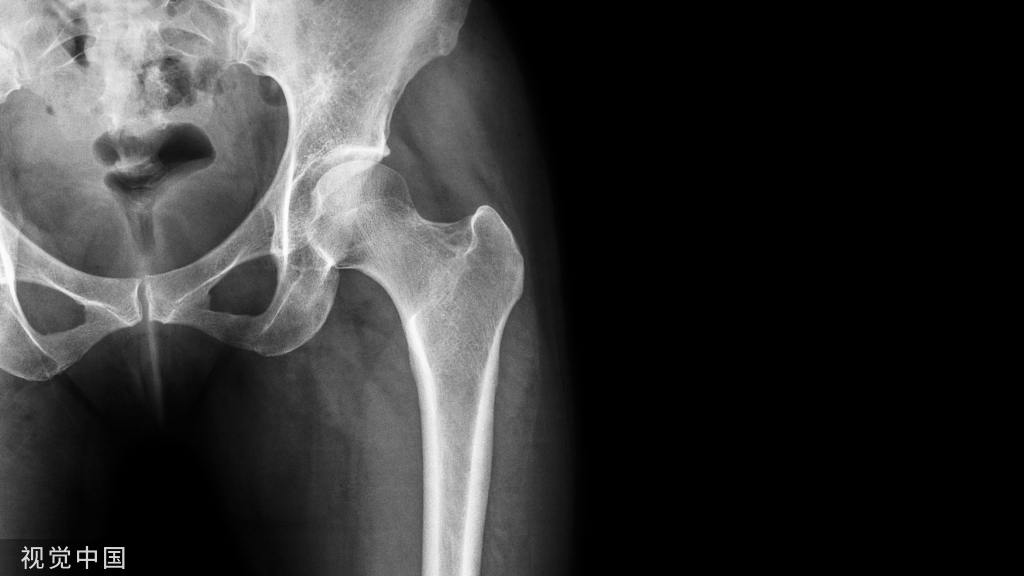

1.骨移植

可用于移植修复骨不连的原材料有自体骨、同种异体骨、人工合成骨和带血运的骨瓣等,目前以自体骨最为常用。自体骨移植是骨移植的金标准。目前自体骨移植具有最低的免疫排斥的风险,并具有强大的骨传导、骨诱导和骨生成等特性,使其成为治疗创伤后骨不连的有效辅助手段。移植到供区的自体骨最好是活骨,也就是骨细胞都是成活的,这样可直接长入供区,速度最快。

对于固定牢靠、断端稳定、骨缺失少的骨折部位,充分的骨移植可有效提高骨不连的治愈率。但受限于供区,对于缺失骨量比较大的骨不连患者,往往不能提供足量的自体骨,还有几率引发供区的各种并发症。同种异体骨或人工骨的获得途径广泛,且不受形状、体积的限制,可有效解决自体骨来源不足的问题,但其生物活性差,对骨折部位只能起到传导支撑的功效,一般不作为常规骨移植材料。

带血运骨瓣可满足更大骨量需求,同时还保证了骨缺损部位的血供,促进患部血液循环重建,并可以提供更多成骨生长因子,对于大量骨缺损的骨不连治疗,无疑是一个有效的选择,但该手术损伤较大,对术者的技术要求较高,同时也造成了供区的骨缺损,因此也不能作为一种常规治疗手段。